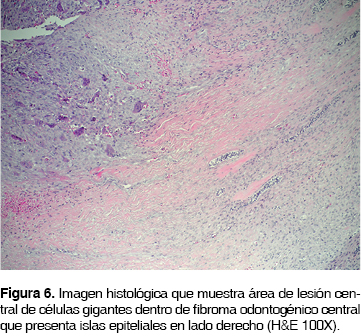

Microscópicamente el tumor estaba conformado por tejido fibrocelular bien vascularizado que formaba fascículos entrelazados de células fusiformes con escasa producción de colágeno, entre las que se observaron abundantes islas y cordones de epitelio odontogénico inactivo. En algunas zonas especialmente hacia la periferia de la lesión, se apreciaron áreas compuestas por tejido fibrocelular altamente vascularizado, en la que se identificaron numerosas células gigantes multinucleadas tipo osteoclasto, dispersas y distribuidas principalmente alrededor de los vasos y zonas de hemorragia intralesional (Figuras 6 y 7).

El caso aquí reportado se muestra histológicamente conformado por tejido fibrocelular bien vascularizado que forma fascículos entrelazados de células fusiformes con escasa producción de fibras colágenas, entre las que se observan abundantes islas y cordones de epitelio odontogénico inactivo. En algunas zonas, se aprecian áreas compuestas por tejido fibrocelular altamente vascularizado, en la que se identifican numerosas células gigantes multinucleadas tipo osteoclasto, dispersas y distribuidas principalmente alrededor de los vasos y zonas de hemorragia intralesional. Estos hallazgos son similares a los descritos en los casos previamente reportados, lo que apoya el concepto de que esta lesión es una entidad en sí misma.